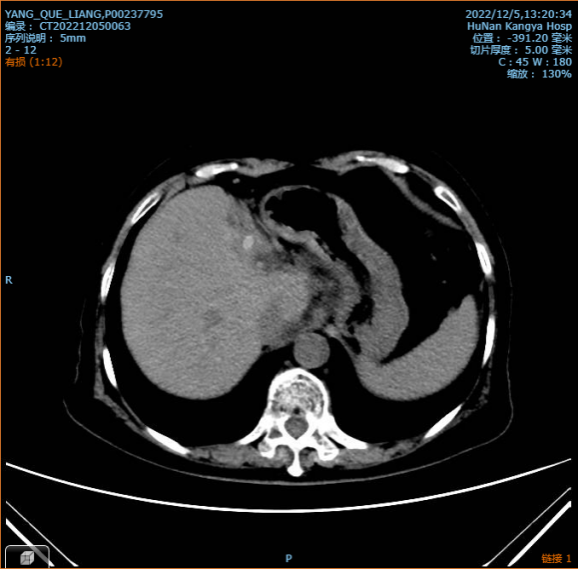

本例手术病人术前检查发现有左肝内胆管多发结石并胆管炎、左肝部分萎缩、胆囊结石胆囊炎、胆源性肝硬化。